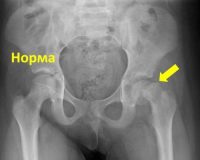

Поражение головки бедренной кости диагностируют врачи-ортопеды-травматологи на основании жалоб, результатов объективного осмотра и визуальных исследований. Основной метод обследования - это рентген тазобедренного сустава. Процедура проводится в 2-х проекциях, наиболее информативной является боковая проекция. Изменения зависят от стадии заболевания.

Во-первых, на рентгеновских снимках разрастающийся хрящ расширяется, а шея становится слоистой из-за чередования участков остеосклероза и остеопороза. Затем выявляется прогрессивное смещение головы, после чего видна линия разрыва. На завершающей стадии наблюдаются признаки консолидации перелома, изменение формы шейки бедренной кости и сужение суставной щели.

Рентгенография дополняется компьютерной томографией тазобедренного сустава, которая проводится для детализации патологических изменений и оценки жизнеспособности головки бедренной кости. Пациентам назначают эндокринолог и дополнительные исследования для диагностики гормональных нарушений. Дифференциальный диагноз ювенильного эпифиза проводится при болезни Пертеса.